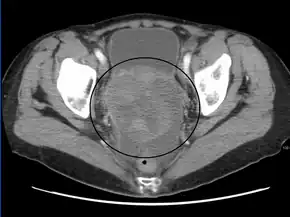

CT scanning is preferred to assess the extent of the tumor in the abdominopelvic cavity, though magnetic resonance imaging can also be used.[21] CT scanning can also be useful for finding omental caking or differentiating fluid from solid tumor in the abdomen, especially in low malignant potential tumors. However, it may not detect smaller tumors. Sometimes, a chest x-ray is used to detect metastases in the chest or pleural effusion. Another test for metastatic disease, though it is infrequently used, is a barium enema, which can show if the rectosigmoid colon is involved in the disease. Positron emission tomography, bone scans, and paracentesis are of limited use; in fact, paracentesis can cause metastases to form at the needle insertion site and may not provide useful results.[22] However, paracentesis can be used in cases where there is no pelvic mass and ascites is still present.[22] A physician suspecting ovarian cancer may also perform mammography or an endometrial biopsy (in the case of abnormal bleeding) to assess the possibility of breast malignancies and endometrial malignancy, respectively. Vaginal ultrasonography is often the first-line imaging study performed when an adnexal mass is found. Several characteristics of an adnexal mass indicate ovarian malignancy; they usually are solid, irregular, multilocular, and/or large; and they typically have papillary features, central vessels, and/or irregular internal septations.[24] However, SCST has no definitive characteristics on radiographic study.[25]

In advanced cancers, where complete removal is not an option, as much tumor as possible is removed in a procedure called debulking surgery. This surgery is not always successful, and is less likely to be successful in women with extensive metastases in the peritoneum, stage- IV disease, cancer in the transverse fissure of the liver, mesentery, or diaphragm, and large areas of ascites. Debulking surgery is usually only done once.[21] Computed tomography (abdominal CT) is often used to assess if primary debulking surgery is possible, but low certainty evidence also suggests fluorodeoxyglucose‐18 (FDG) PET/CT and MRI may be useful as an addition for assessing macroscopic incomplete debulking.[63] More complete debulking is associated with better outcomes: women with no macroscopic evidence of disease after debulking have a median survival of 39 months, as opposed to 17 months with less complete surgery.[19] By removing metastases, many cells that are resistant to chemotherapy are removed, and any clumps of cells that have died are also removed. This allows chemotherapy to better reach the remaining cancer cells, which are more likely to be fast-growing and therefore chemosensitive.[22]